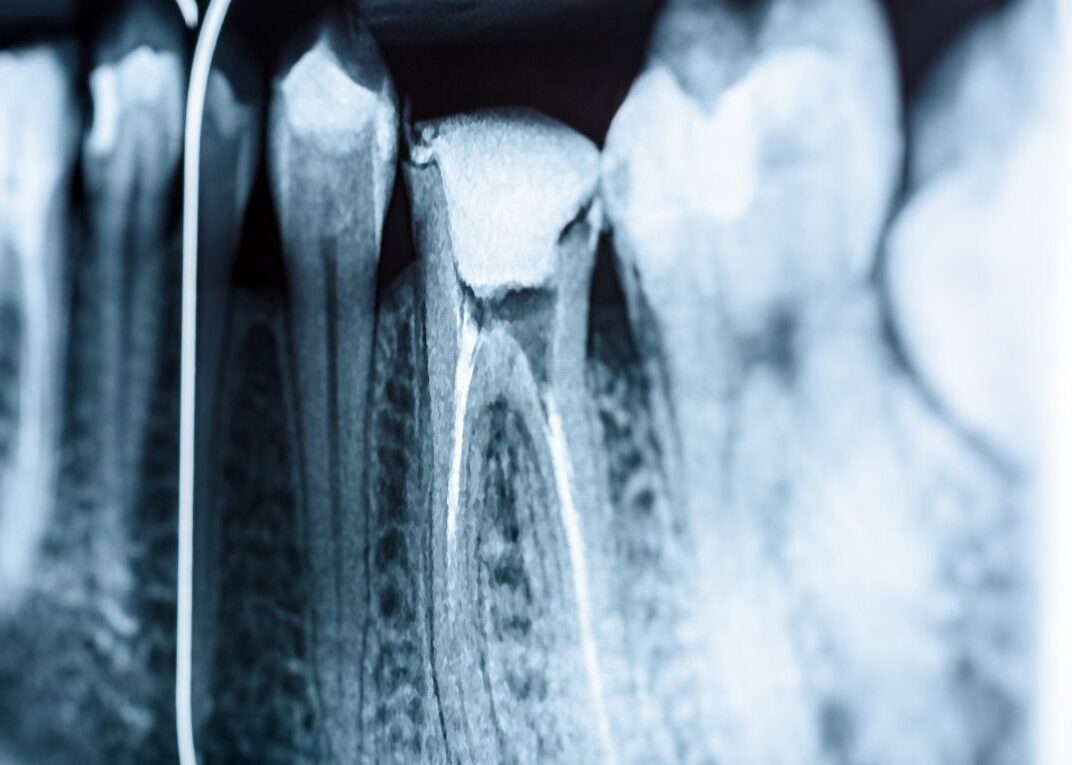

- Diagnostyka i przygotowanie: Podstawą jest dokładne RTG zęba, a często także tomografia CBCT, aby dokładnie ocenić kanały zęba.

- Opracowanie mechaniczne: Aby zapewnić skuteczne leczenie kanałowe, stosuje się mikroskop endodontyczny. Taki zabieg endodontyczny pod mikroskopem pozwala idealnie widzieć wszystkie kanały korzeniowe w powiększeniu.